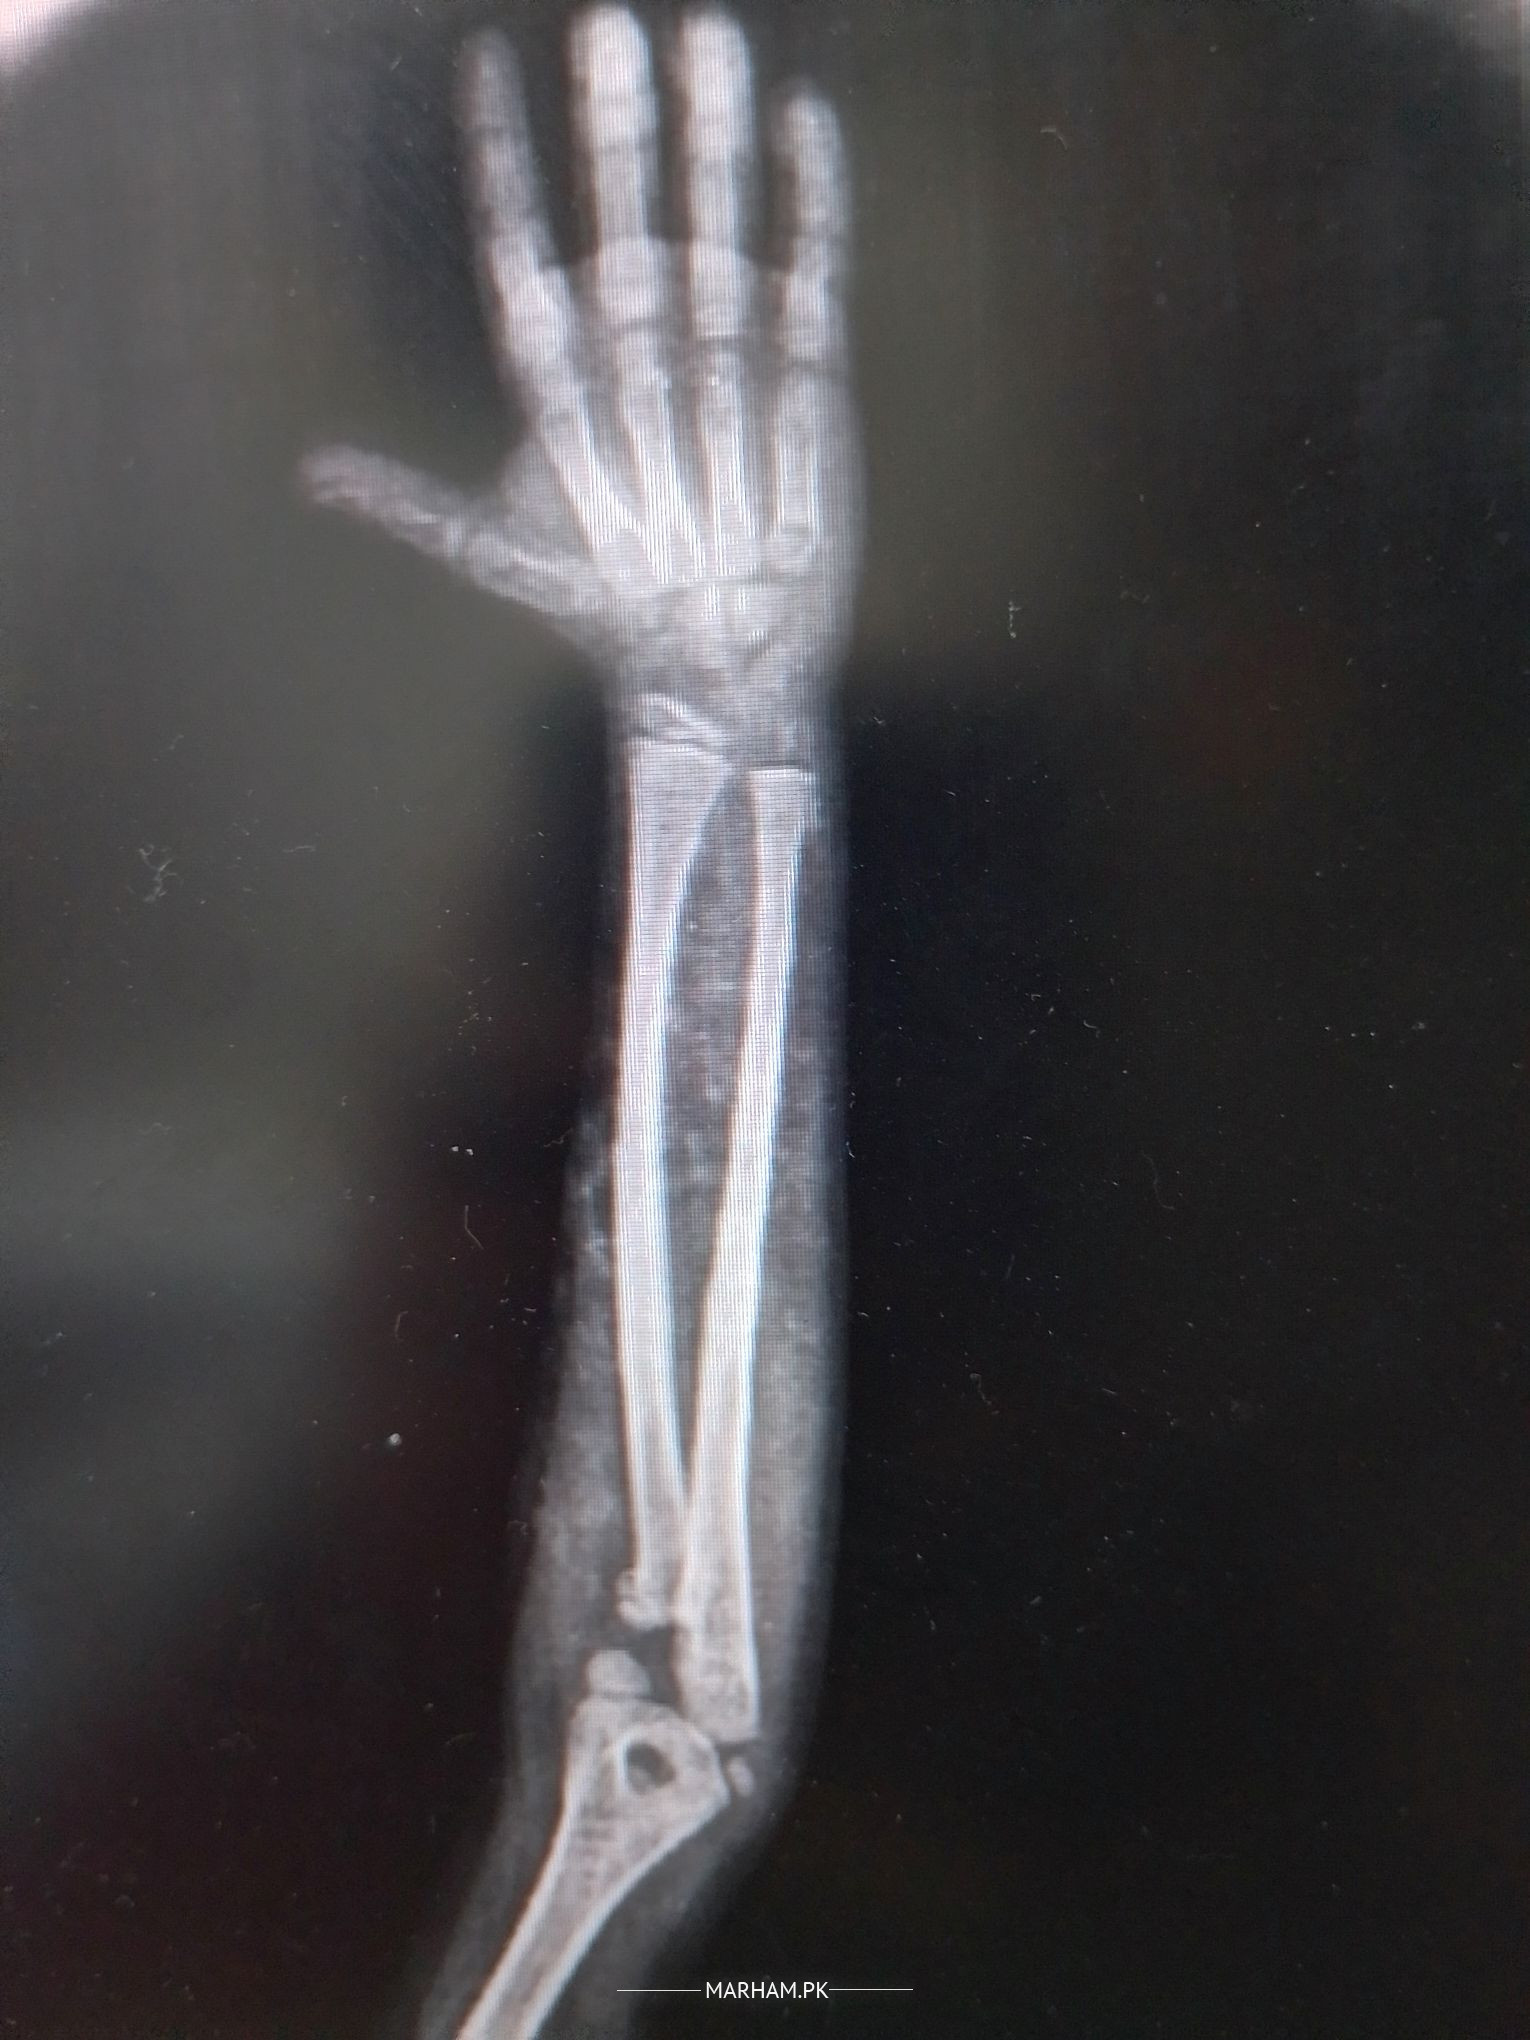

x-ray shows doubtful fracture of Head of radius

For Treatment History and Examination is important.On xrays radius (bone on outer side)is short and head seems to be fractured.

most likely treated by jarrah.

For my Fellow colleagues:

My concern here is the "corner fracture".

It would raise doubts about Non Accidental Injury.

fracture hai head of radius but operation ki zrurat ni hai. 1 week plaster and then start moving elbow takay stiffness na aaiy.

ap ki beti ki koni kay pass say haddi tooti hay.is ko jagah par bithana parta hay jis kay liyay pehlay ap ko kisi achay haddi kay doctor ko dikhana hoga